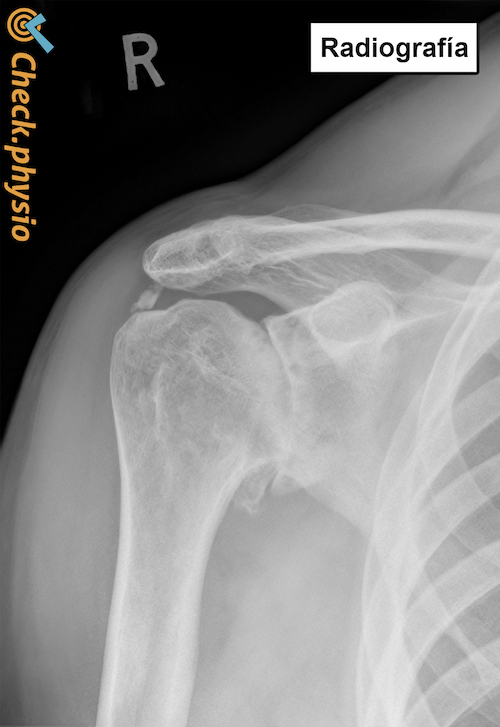

Desgaste de la articulación del hombro / artrosis del hombro

Fisioterapia en línea para Artrosis del hombro

¿Lleva sufriendo estos síntomas desde hace tiempo? ¿Y no mejoran si descansa o evita los movimientos dolorosos? Entonces tiene sentido hacer algunos ejercicios cada día para mejorar los síntomas de forma gradual y permanente.

Nuestro programa de ejercicios en línea para Artrosis del hombro ha sido elaborado por fisioterapeutas experimentados. Nuestro enfoque ha demostrado su eficacia y tiene una base científica.